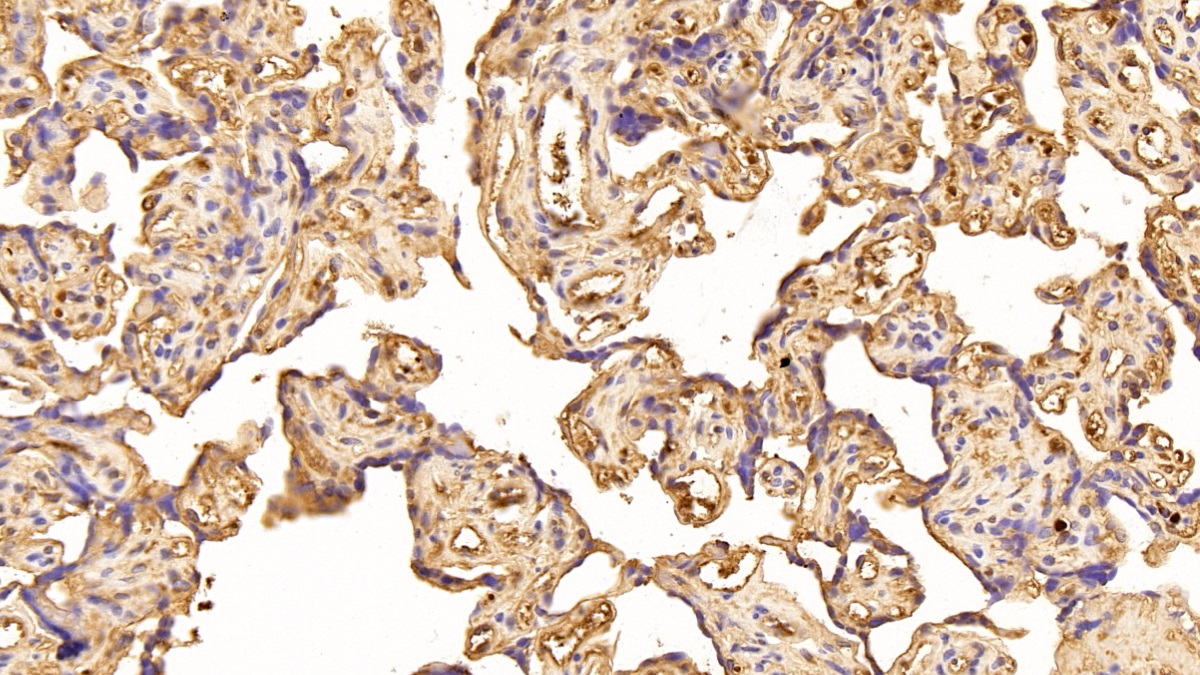

Использование высококачественных первичных антител является неотъемлемым условием получения точных и воспроизводимых результатов в современных научных исследованиях. Например, в рамках онкологического исследования удалось достоверно идентифицировать экспрессию белка PD-L1, что сыграло ключевую роль в оценке потенциальной эффективности иммунотерапии. Применение надежных антител обеспечило стабильность сигнала и высокую специфичность детекции, что позволило получить данные, пригодные для публикации в рецензируемых научных изданиях.